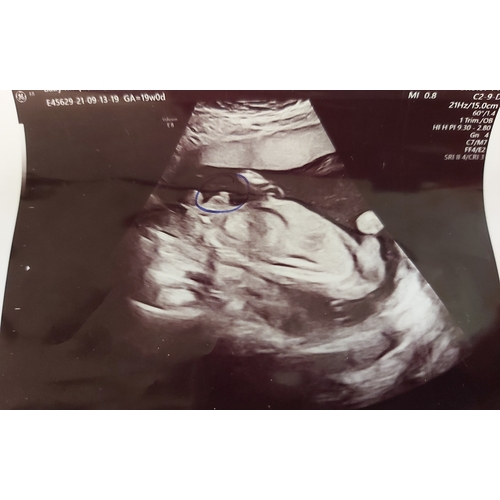

Ja hoor hier hetzelfde verhaal! Eerst een meisje met 16+3 en met 19+1 een jongen ! Ik ben toen naar een ander echo centrum geweest voor een second opinie met 21+3 en daar echt 100% een jongen gezien!

Komt vaker voor. Jongetjes ontwikkelen zich soms later pas waardoor je het piemeltje niet ziet. In beginsel lijkt elke baby een meisje. Rond 14 weken bestaat inderdaad de kans dat hij nog niet zo ver ontwikkeld was. Zie dat je echo met 19 weken is, dan is het idd al wel af.

Ik zou zeggen dat je een zoontje krijgt oo basis van de echo’s.